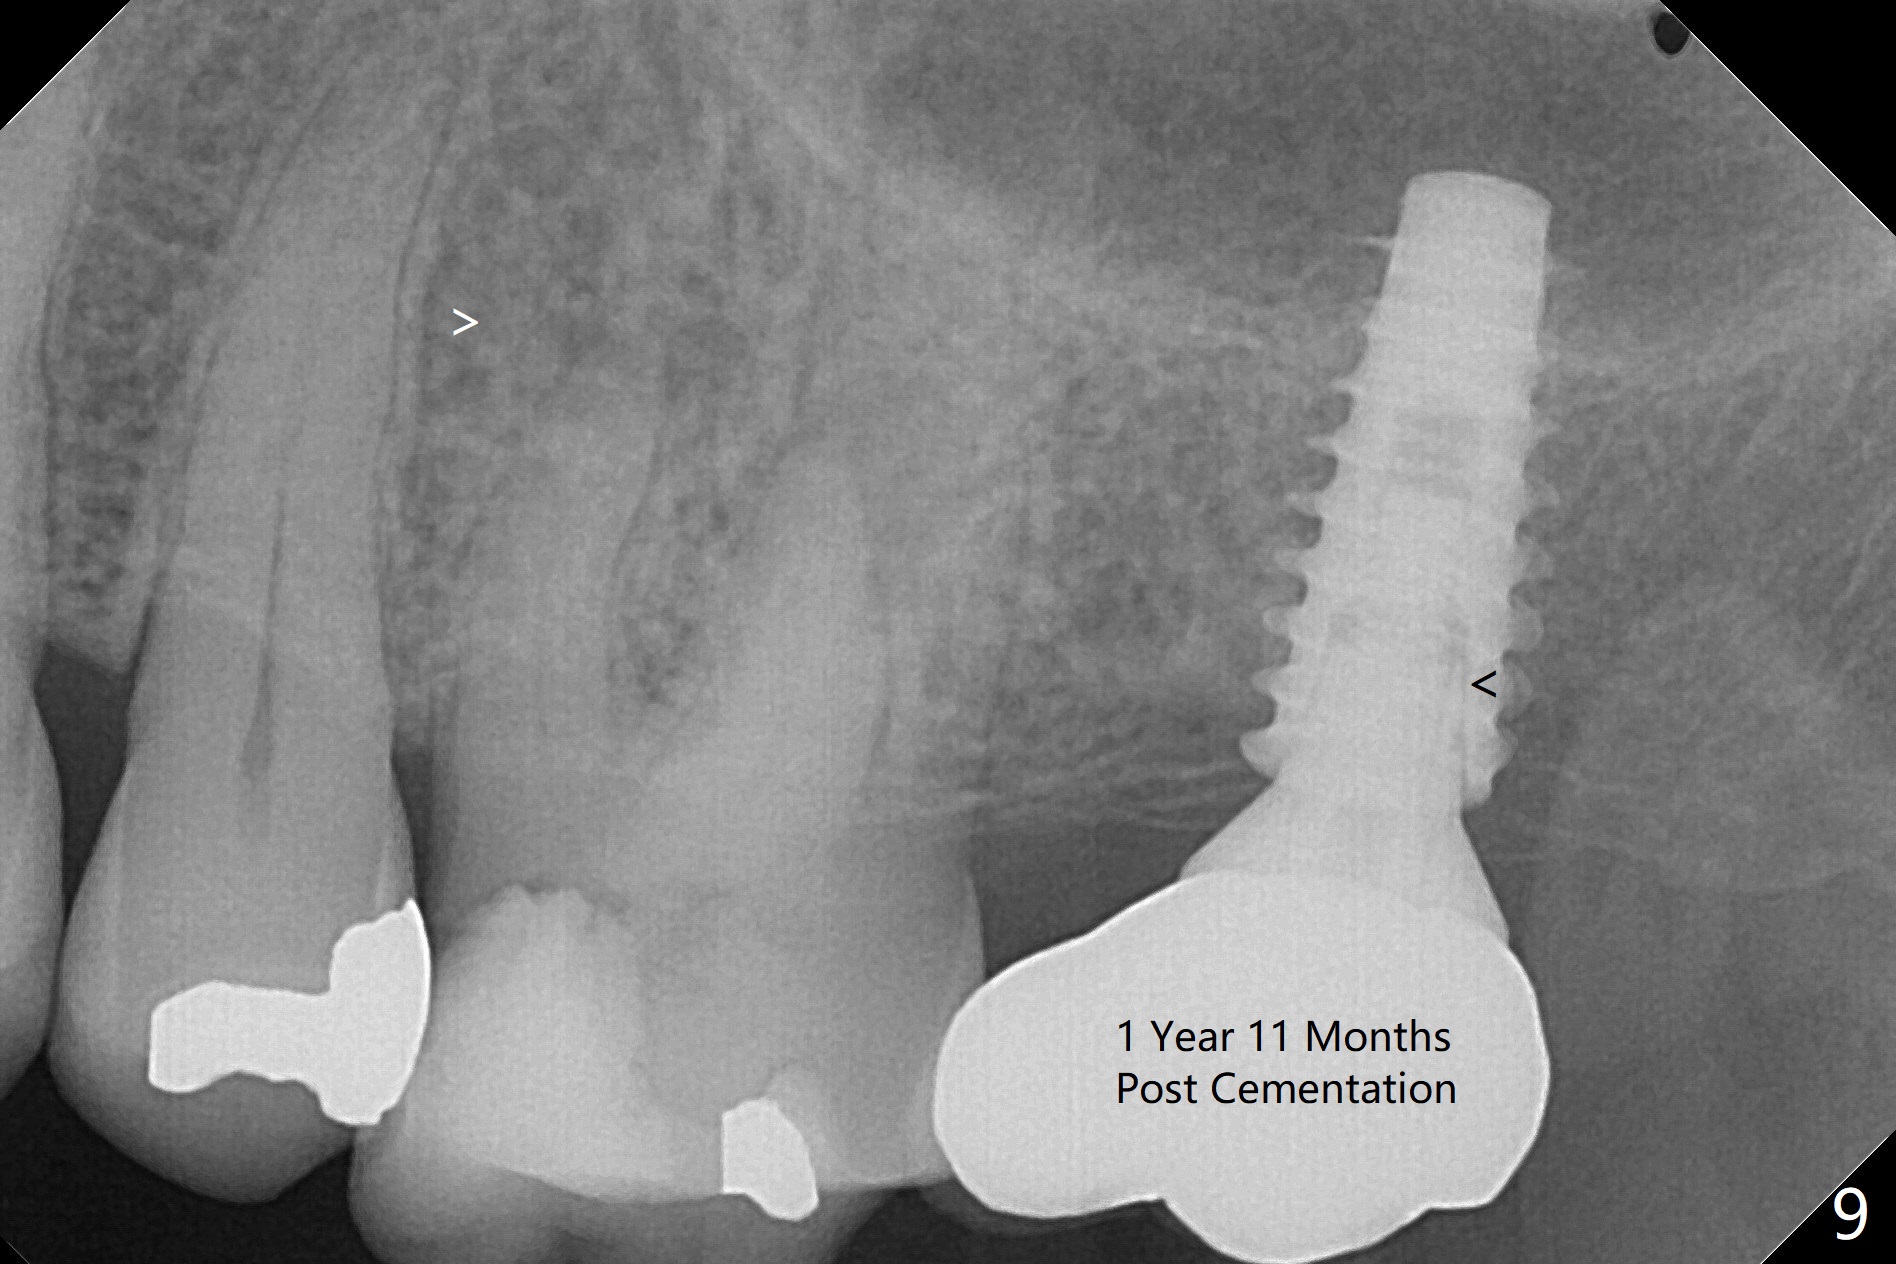

The ridge is pointed at the site of #15 (Fig.1). A 1.2 mm initial drill is used to start osteotomy for 10 mm, followed by an incision over the ridge mesiodistally for ~ 8 mm. After tapping the #15 C blade, the 1st Bone Expander 1.0/1.6 mm) is inserted for ~ 11 mm (Fig.2, 20 Ncm). Bone expansion continues until #4 Expander (2.4/3.7 mm, Fig.3). When 4x11 mm and 4.5x11 mm dummy implants are placed (Fig.4), insertion torque remains 20 Ncm. Following placing allograft with 3-4 amalgam carriers, a 5x11 mm IBS implant is placed with 20 Ncm (Fig.5,6). In fact the implant turns when an abutment is placed. When the implant is re-inserted, torque decreases to 10 Ncm. Instead a healing screw is placed. The low torque value is due to soft bone and failure to underprep. #4 Expander (Fig.3) seems larger than 4.5 mm implant (Fig.4). #3 Expander (1.7/3.1 mm) should have been used prior to definitive implant placement. The implant appears to have osteointegrated 3 months postop (Fig.7); impression is taken. The bone density at the crest increases 1.5 years post cementation (Fig.8 *, as compared to Fig.6), although there is mild bone loss. Implant placement should be deep when bone expansion is carried out. The tooth #14 develops a buccal fistula, corresponding to periapical radiolucency of the mesiobuccal root (Fig.9 white >). The abutment of #15 may be incompletely seated (black <). PA taken when RCT of #14 is finished does not show the incomplete seating of the abutment (Fig.10). Since there appears no history of abutment screw loosening, the abutment is not reseated when #14 is prepared for crown. Recall 3 years 7 months post cementation shows incomplete seating of the abutment (Fig.11 >). After crown proximal reduction (Fig.12 *) and clockwise turn of the crown, the abutment appears to be completely seated. When the case returns from lab, the separate crown and abutment cannot be connected to the fixture because of soft tissue adaptation and change in a month. The abutment is reseated to the fixture analog in the model and the crown is recemented with temp bond (in case of misalignment) while making sure that the crown has the best proximal contact with the neighboring crown. With the abutment and crown in a unit, it is much easier to reseat the abutment with normal proximal contact. The torque is 20 Ncm. The access hole is closed with Cavit.